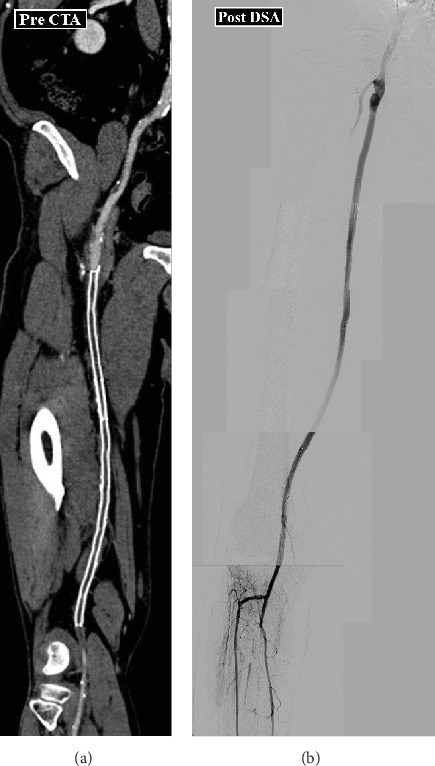

我们提出一个60岁的男子跛行在他的右脚的情况下;患者1年前接受过右股浅动脉(SFA)支架植入术。计算机断层血管造影提示支架闭塞右侧SFA,血栓被认为是引起闭塞的原因。为了避免远端栓塞,我们通过经踝关节介入进行病变再通。首先,我们对病变进行抽吸;然而,血栓仍然存在。其次,我们进行了“超级抓住血栓并保持”技术并清除了几个血栓。最后,我们使用药物包覆气球作为治疗病变的最后设备。两年后,超声检查发现右侧SFA打开。

We present a case of a 60-year-old man with claudication in his right foot; the patient had received stent-graft implantation for the right superficial femoral artery (SFA) 1 year ago. Computed tomography angiography suggested stent occlusion of the right SFA, and a thrombus was considered to cause occlusion. To avoid distal embolization, we performed lesion recanalization via a trans-ankle intervention. First, we performed aspiration for the lesion; however, the thrombus persisted. Second, we performed the "Super Grab a Clot and Hold ON" technique and removed several thrombi. Finally, we used drug-coated balloons as a final device for the lesion. Two years later, the right SFA was found open upon an ultrasonography.